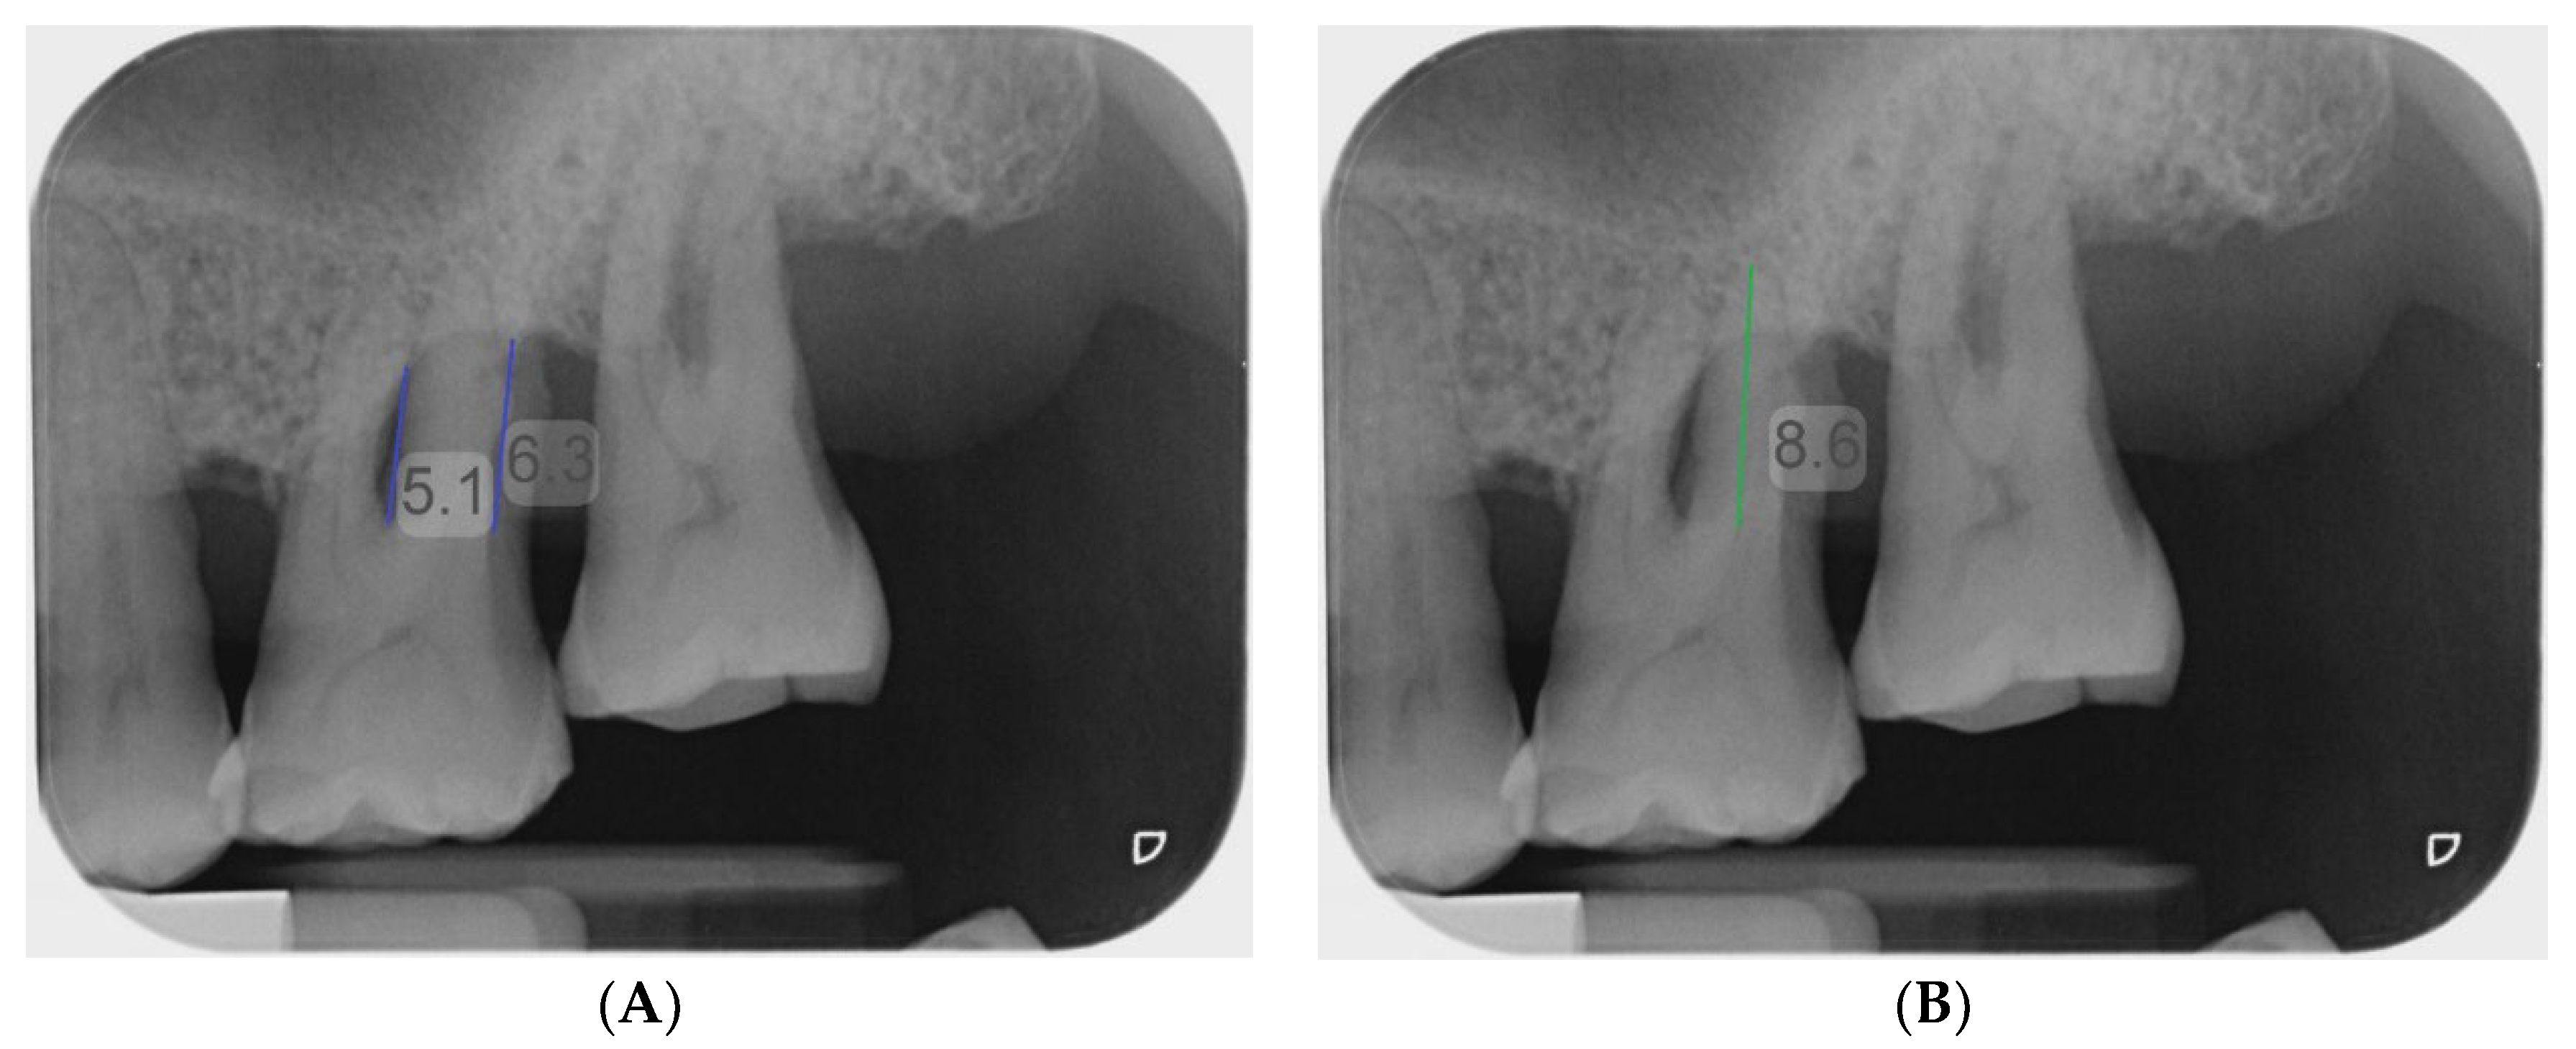

Figure 1. (A) Case example with a complete set of clinical periodontal record, periapical radiograph, and CBCT DICOM files as viewed on Romexis Viewer (Planmeca). (B) The CBCT viewer axis was first aligned along the long axis of the tooth at the sagittal section and coronal section. At the axial section, the sagittal and coronal planes were adjusted to intersect the canal orifices of the two roots bounding the concerned furcation involvement.

The examiners were briefed on the study procedures and the furcation classification systems used in the assessment. Each examiner was provided with clinical periodontal chartings and periapical radiographs. All periapical radiographs were imported into the Romexis Viewer software (Planmeca) and were analysed on the same computer screen (Microsoft Surface Pro 7). On the periapical radiographs, the examiners were asked to measure the vertical bone loss in the furcation area (to the nearest 0.1 mm) using the linear measurement tool in Romexis Viewer with the clinical periodontal charting as a reference (Figure 1 and Figure 3A). To diagnose the FI according to the modified vertical subclassification, the examiners were also asked to measure the length of the shorter root bounding the furcation (which was pre-determined as part of the gold standard assessment) (Figure 3B). All data were recorded on a data collection form in Microsoft Excel(Excel 2016 Inc, Redmond, Washington, USA).